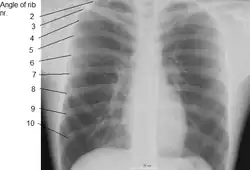

Las costillas humanas generalmente son 12 a cada lado (24 en total): 7 verdaderas o esternales (I-VII), 3 falsas o asternales (VIII-X), y 2 flotantes (XI y XII), en forma de arco con un cuerpo con dos caras, externa e interna; dos bordes, superior e inferior; y dos extremos, posterior y anterior.

- Ángulo: La separación entre el ángulo y el tubérculo es progresivamente mayor de la segunda a la décima costillas. La porción entre el ángulo y el tubérculo es redonda, áspera e irregular, y sirve para la inserción del músculo dorsal diente vértebra torácica; falta este tubérculo en los últimos 3 pares de costillas.